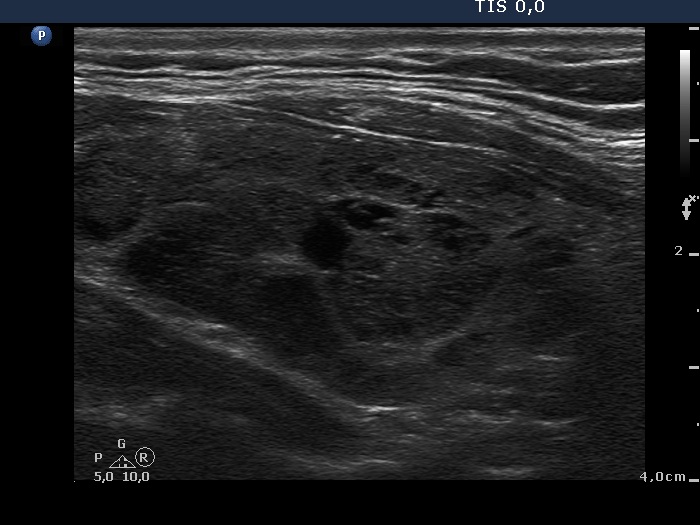

Study on 100 consecutive patients with thyroid nodule - case 001

Three years after the first examination (ultrasonographic picture 7)

Left lobe, longitudinal scan. The pattern is identical to that was seen 3 years ago.